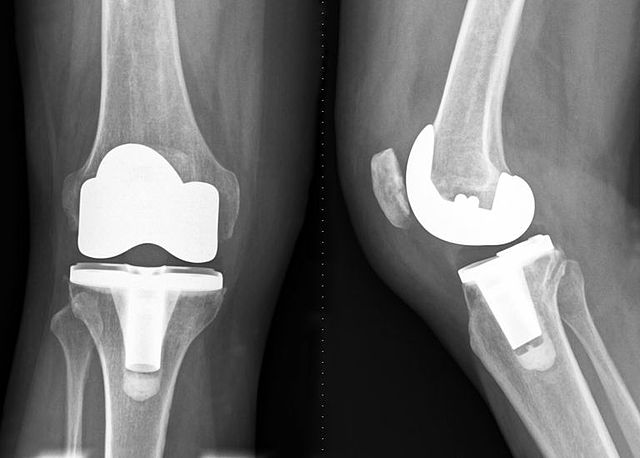

• Inspiration of the Development of Knee Replacements

Inspiration of the Development of Knee Replacements

In the early 1960s Sir John Charnley inspired development of the Condylar knee replacement.

• First Total Knee Replacement

First Total Knee Replacement

Dr. Gunston who worked with Sir John Charnley went on to implant the first polycentric knee with an unhinged knee design which replaced both the medial and lateral sides, therefore making it the first total knee replacement. This implant was designed to be a game changer for patients with arthritis where other medicine approaches such as physio therapy had failed. The implant recreated how real knees worked and was the first one to contain all the correct anatomically shaped parts in the knee.